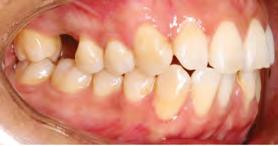

en paciente adulto tratado con extracciones de primeros molares permanentes. Reporte de caso

Dentista y Paciente 52 Sonriendo al futuro